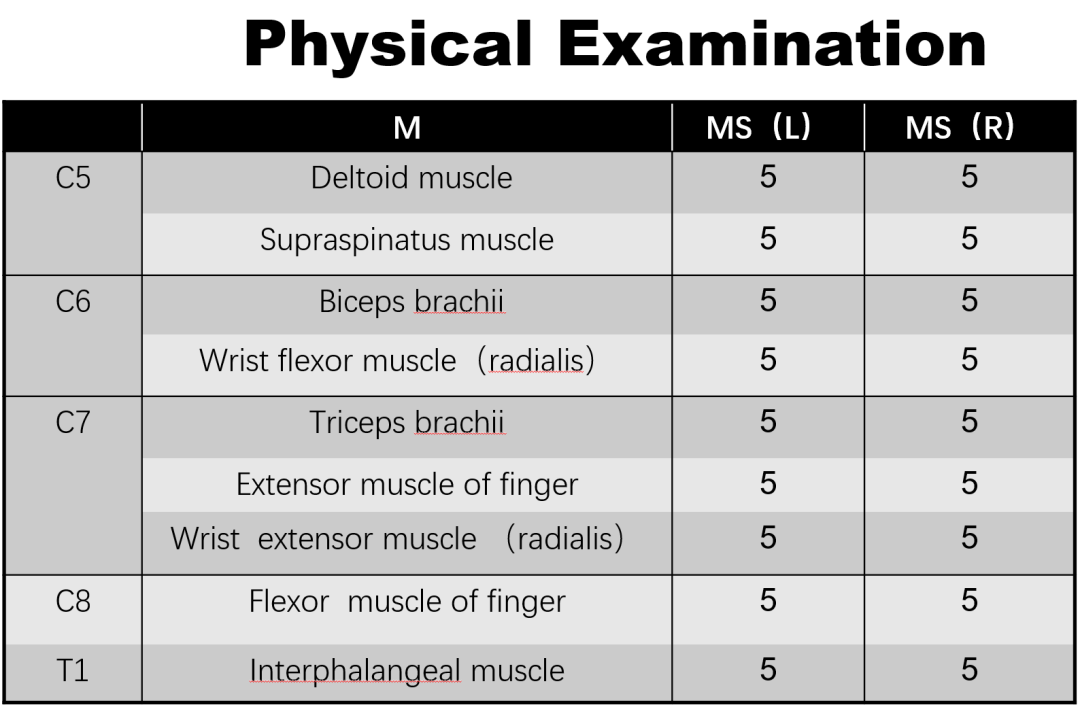

男,76岁

现病史:

腰背痛2年,加重伴腰部后凸不能直立半年